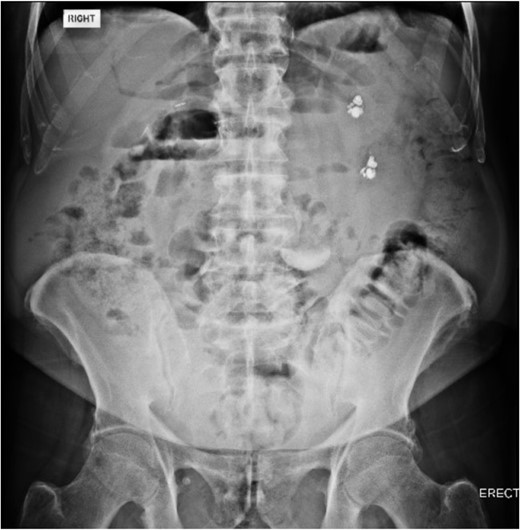

An 80 year old male presented to the emergency department after accidentally swallowing his hearing aids. On presentation he was pain free, hemodynamically stable, and had a soft abdomen. He had a background of type-2 diabetes, rheumatoid arthritis and diverticulitis. The hearing aids were powered by lithium battery. X-ray found two foreign bodies in the left upper abdomen (Fig. 1). After assessment in the emergency department, he returned home to await their natural passage. One hearing aid was found in his stools the following day, but he represented three weeks later as the second hearing aid remained unaccounted for. He underwent repeat abdominal x-ray and CT, which found the hearing aid retained within a presumed distal duodenal diverticulum (Figs 2 and 3). He was booked a push enteroscopy the following day.

Abdominal CT identifying one hearing aid in a jejunal diverticulum 3 weeks after initial presentation – axial view.